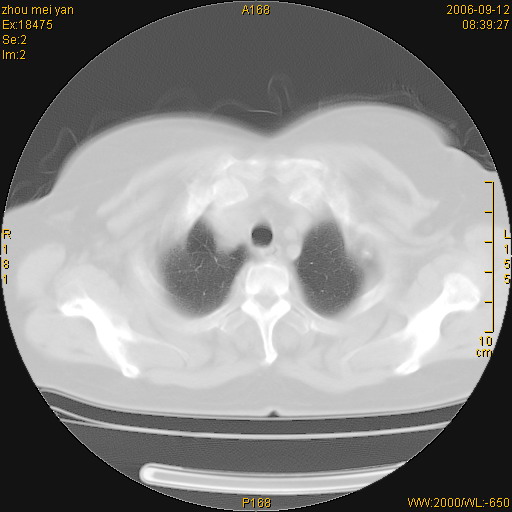

患者、女、55岁。因心率失常住院检查ct发现胸部多发结节。腹部b超肝、胆、胰、脾、肾、子宫附件未见异常。无结核病史,无粉尘接触史。请大家来会诊。谢谢!

病变位于胸膜,多发结节,边界清楚,内见小结节状钙化。其它未见异常。

双侧胸膜多发结节,形态不规则,边缘较清楚,每一个结节中心似乎都有钙化点的特征,与胸膜广基相切。临床无结核病史,无粉尘接触史。

影像表现十分有特点:双侧肋胸膜及膈胸膜广泛散在分布大小在2至6mm左右,较大病灶中心可见钙化。

考虑恶性胸膜间皮瘤可能性大,病灶位于胸膜,以宽基地与胸膜相连,呈结节样改变,部分病灶内可见点状钙化影。请各位老师多多指导!

双侧肋胸膜及膈胸膜广泛散在分布大小不等结节影,较大病灶中心可见钙化。